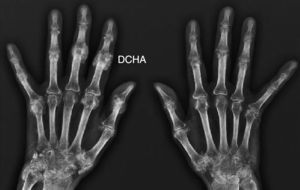

Presentamos el caso de una mujer de 63 años, ama de casa, que presentaba antecedentes personales de diabetes mellitus tipo 2, hipertensión arterial y dislipidemia con buen control, bajo tratamiento con metformina, enalapril y atorvastatina. No refería antecedentes familiares de interés, hábitos tóxicos ni contactos con animales. Es remitida para valoración de poliartralgias de ritmo mixto, de predominio mecánico, en pequeñas articulaciones de las manos y los pies, de 2 años de evolución, sin «hinchazón», pero con rigidez articular matutina en las manos de aproximadamente 2h. En la ananmesis por órganos destacaba el desarrollo de tos seca y disnea de moderados esfuerzos desde el inicio de las artralgias, así como la aparición de fenómeno de Raynaud en las manos, sin lesiones vasculíticas desde hacía un año. El apetito y el peso estaban conservados, sin fiebre. A la exploración física la paciente tenía buen estado general, eupneica en reposo, sin adenopatías ni lesiones cutáneas; la auscultación cardiorrespiratoria puso de manifiesto crepitantes en «velcro» hasta campos medios, sin otros hallazgos; en la exploración reumatológica se evidenció dolor a la flexoextensión de las muñecas, sin sinovitis y pequeñas tumoraciones frías indoloras semiinduradas en algunas articulaciones metacarpofalángicas e interfalángicas de las manos (fig. 1); el resto de las áreas articulares no mostró dolor, limitación del rango de movilidad ni tumefacción articular. La exploración neurovascular fue compatible con la normalidad, sin dolor a la presión de la musculatura de las extremidades ni impotencia funcional. Los datos de laboratorio mostraron los siguientes resultados: hemograma, bioquímica, reactantes de fase aguda, aldolasa, creatincinasa, hormonas tiroideas y paratohormona dentro de la normalidad; anticuerpos anti histidil-RNAt sintetasa (anti-Jo-1) positivos a título alto, con el resto del estudio de autoinmunidad negativo (factor reumatoide, anticuerpos antipéptidos citrulinados, antinucleares, anti-U1-RNP, antiRo, anticitoplasmáticos, antiendomisio). El estudio electromiográfico de miembros superiores e inferiores no detectó datos de miopatía inflamatoria. Las pruebas de imagen realizadas incluyeron: radiografías de los codos, las manos (fig. 2), la pelvis, las rodillas y los pies. Se observaron únicamente depósitos cálcicos en áreas periarticulares de las manos junto con osteopenia, sin apreciarse erosiones en ninguna articulación. La radiografía y la tomografía torácica de alta resolución mostraron un patrón reticular compatible con neumopatía intersticial. Se realizó una biopsia pulmonar, con el diagnóstico final de neumopatía intersticial usual, en estadio de fibrosis. En función de los datos clínicos y los resultados de las pruebas complementarias realizadas se concluyó el diagnóstico de síndrome antisintetasa.

Con respecto a las manifestaciones reumatológicas del síndrome antisintetasa, la afectación poliarticular simétrica no erosiva es la más frecuente, pudiendo asociar calcinosis distal. Nuestra paciente no refería episodios de inflamación articular y no observamos sinovitis en la exploración. Dado que la calcinosis suele desarrollarse en áreas donde previamente ha habido un proceso inflamatorio, en nuestro caso es posible que la calcinosis sea el resultado de un proceso inflamatorio subclínico previo (atendimos a la paciente tras 2 años de sintomatología).

Una publicación reciente de la Clínica Mayo4 estudió la relación entre calcinosis y diversas conectivopatías. La enfermedad reumatológica que con mayor frecuencia se asoció a calcinosis fue la dermatomiositis, seguida de la esclerosis sistémica, la enfermedad mixta del tejido conectivo y el lupus eritematoso sistémico. Aproximadamente entre un 3-5% de los pacientes con síndrome antisintetasa puede clasificarse como síndromes de superposición con otras conectivopatías como la artritis reumatoide, el lupus eritematoso sistémico, la esclerosis sistémica o el síndrome de Sjögren5. Los datos clínicos, analíticos, de autoinmunidad, las pruebas de imagen y el estudio neurofisiológico descartaron cualquiera de estas conectivopatías, así como un síndrome de superposición con artritis reumatoide como responsable de la calcinosis que presentó nuestra paciente. Otro aspecto interesante de nuestro caso es que solo apreciamos calcinosis periarticular en las manos, pues habitualmente la calcinosis asociada a las conectivopatías suele afectar de modo multifocal a las áreas de extensión articular de las extremidades. Otros procesos que pueden causar calcinosis, aunque en nuestro paciente se descartaron, son enfermedades metabólicas (nefropatía crónica, hiperparatiroidismo e hipervitaminosis D), infecciones parasitarias como la cistercorcosis y procesos traumáticos musculares o incluso infiltraciones periarticulares.

El interés de nuestro caso radica en la forma de presentación de la calcinosis localizada exclusivamente en las manos, sin evidencia previa de actividad inflamatoria articular ni periarticular en un síndrome antisintetasa anti-Jo-1 sin afectación muscular.